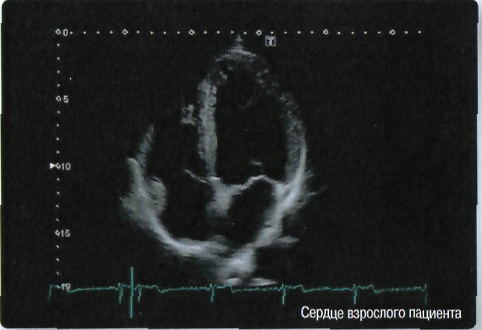

Кардиология:

Да

• Отображение физиологической информации ЭКГ/ФКГ (фонокардиографии - графической регистрации сердечных тонов и шумов);

• Стресс-эхо исследования с фармакологической и физической нагрузкой;

• Стресс-эхо для исследований с фармакологической и физической нагрузкой и др.